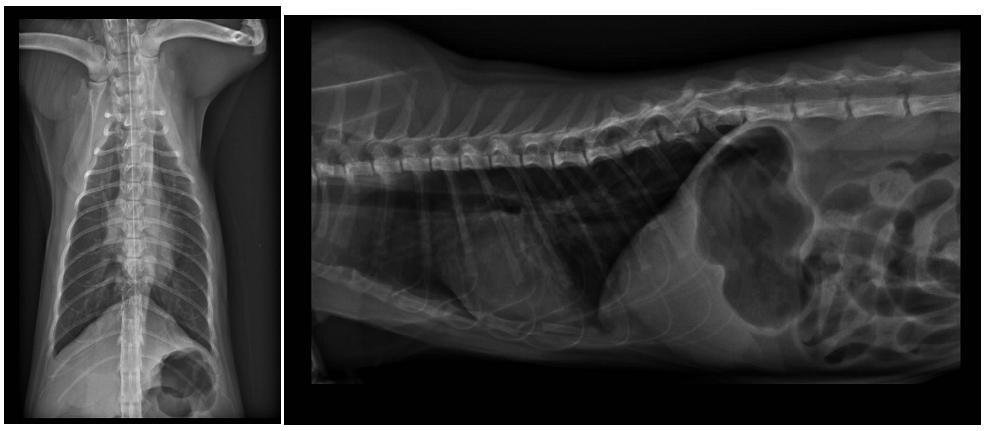

1.貓瘟快篩 600

3.X-ray 400*2